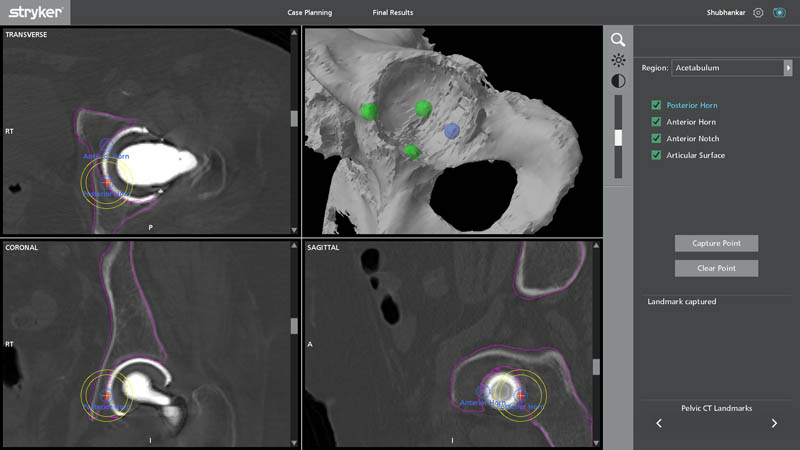

Pelvic CT Landmarks

Segmentation is an advanced imaging and planning process where CT-based data is converted into highly detailed 3D anatomical models. This allows the surgeon to:

- Identify exact areas of bone loss

- Plan implant removal safely

- Customize implant size and placement

- Avoid vital structures

- Anticipate surgical challenges before entering the OT